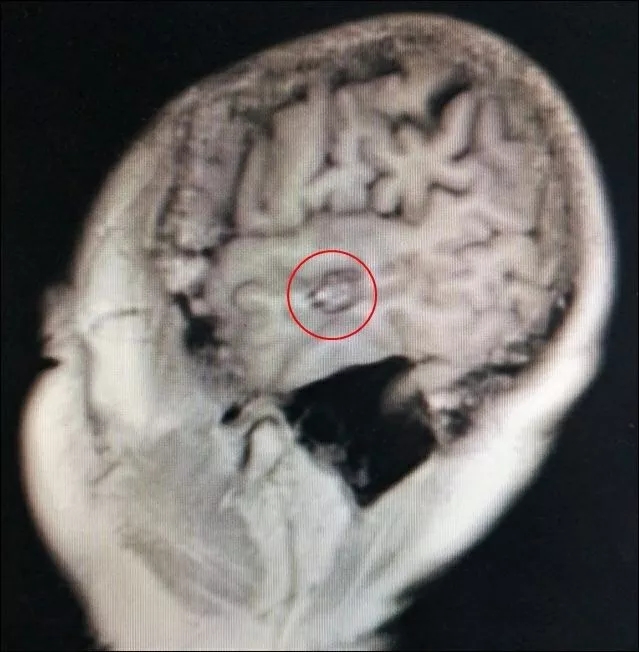

神经外科李世清医师,为患者进行进一步检查。术前MRI提示左侧颞叶可见类圆形混杂信号占位,病灶周围环形低信号影,提示曾反复出血后含铁血黄素带沉积,水抑制相可见病灶位于左侧外侧裂下方,增强相未见明显强化。初步考虑为海绵状血管瘤,直径约1cm ,易反复出血致头痛,癫痫。

CT核查显示术前定位精准

如何将藏在脑实质内的小病灶精准找到并切除,在没有术中导航的情况下,对脑部手术医师来讲,的确是个难题和挑战。神经外科宋增亮主任和李世清医师仔细阅读和分析术前MRI资料,利用传统的定位技术,标记出侧裂,从而定位病灶。